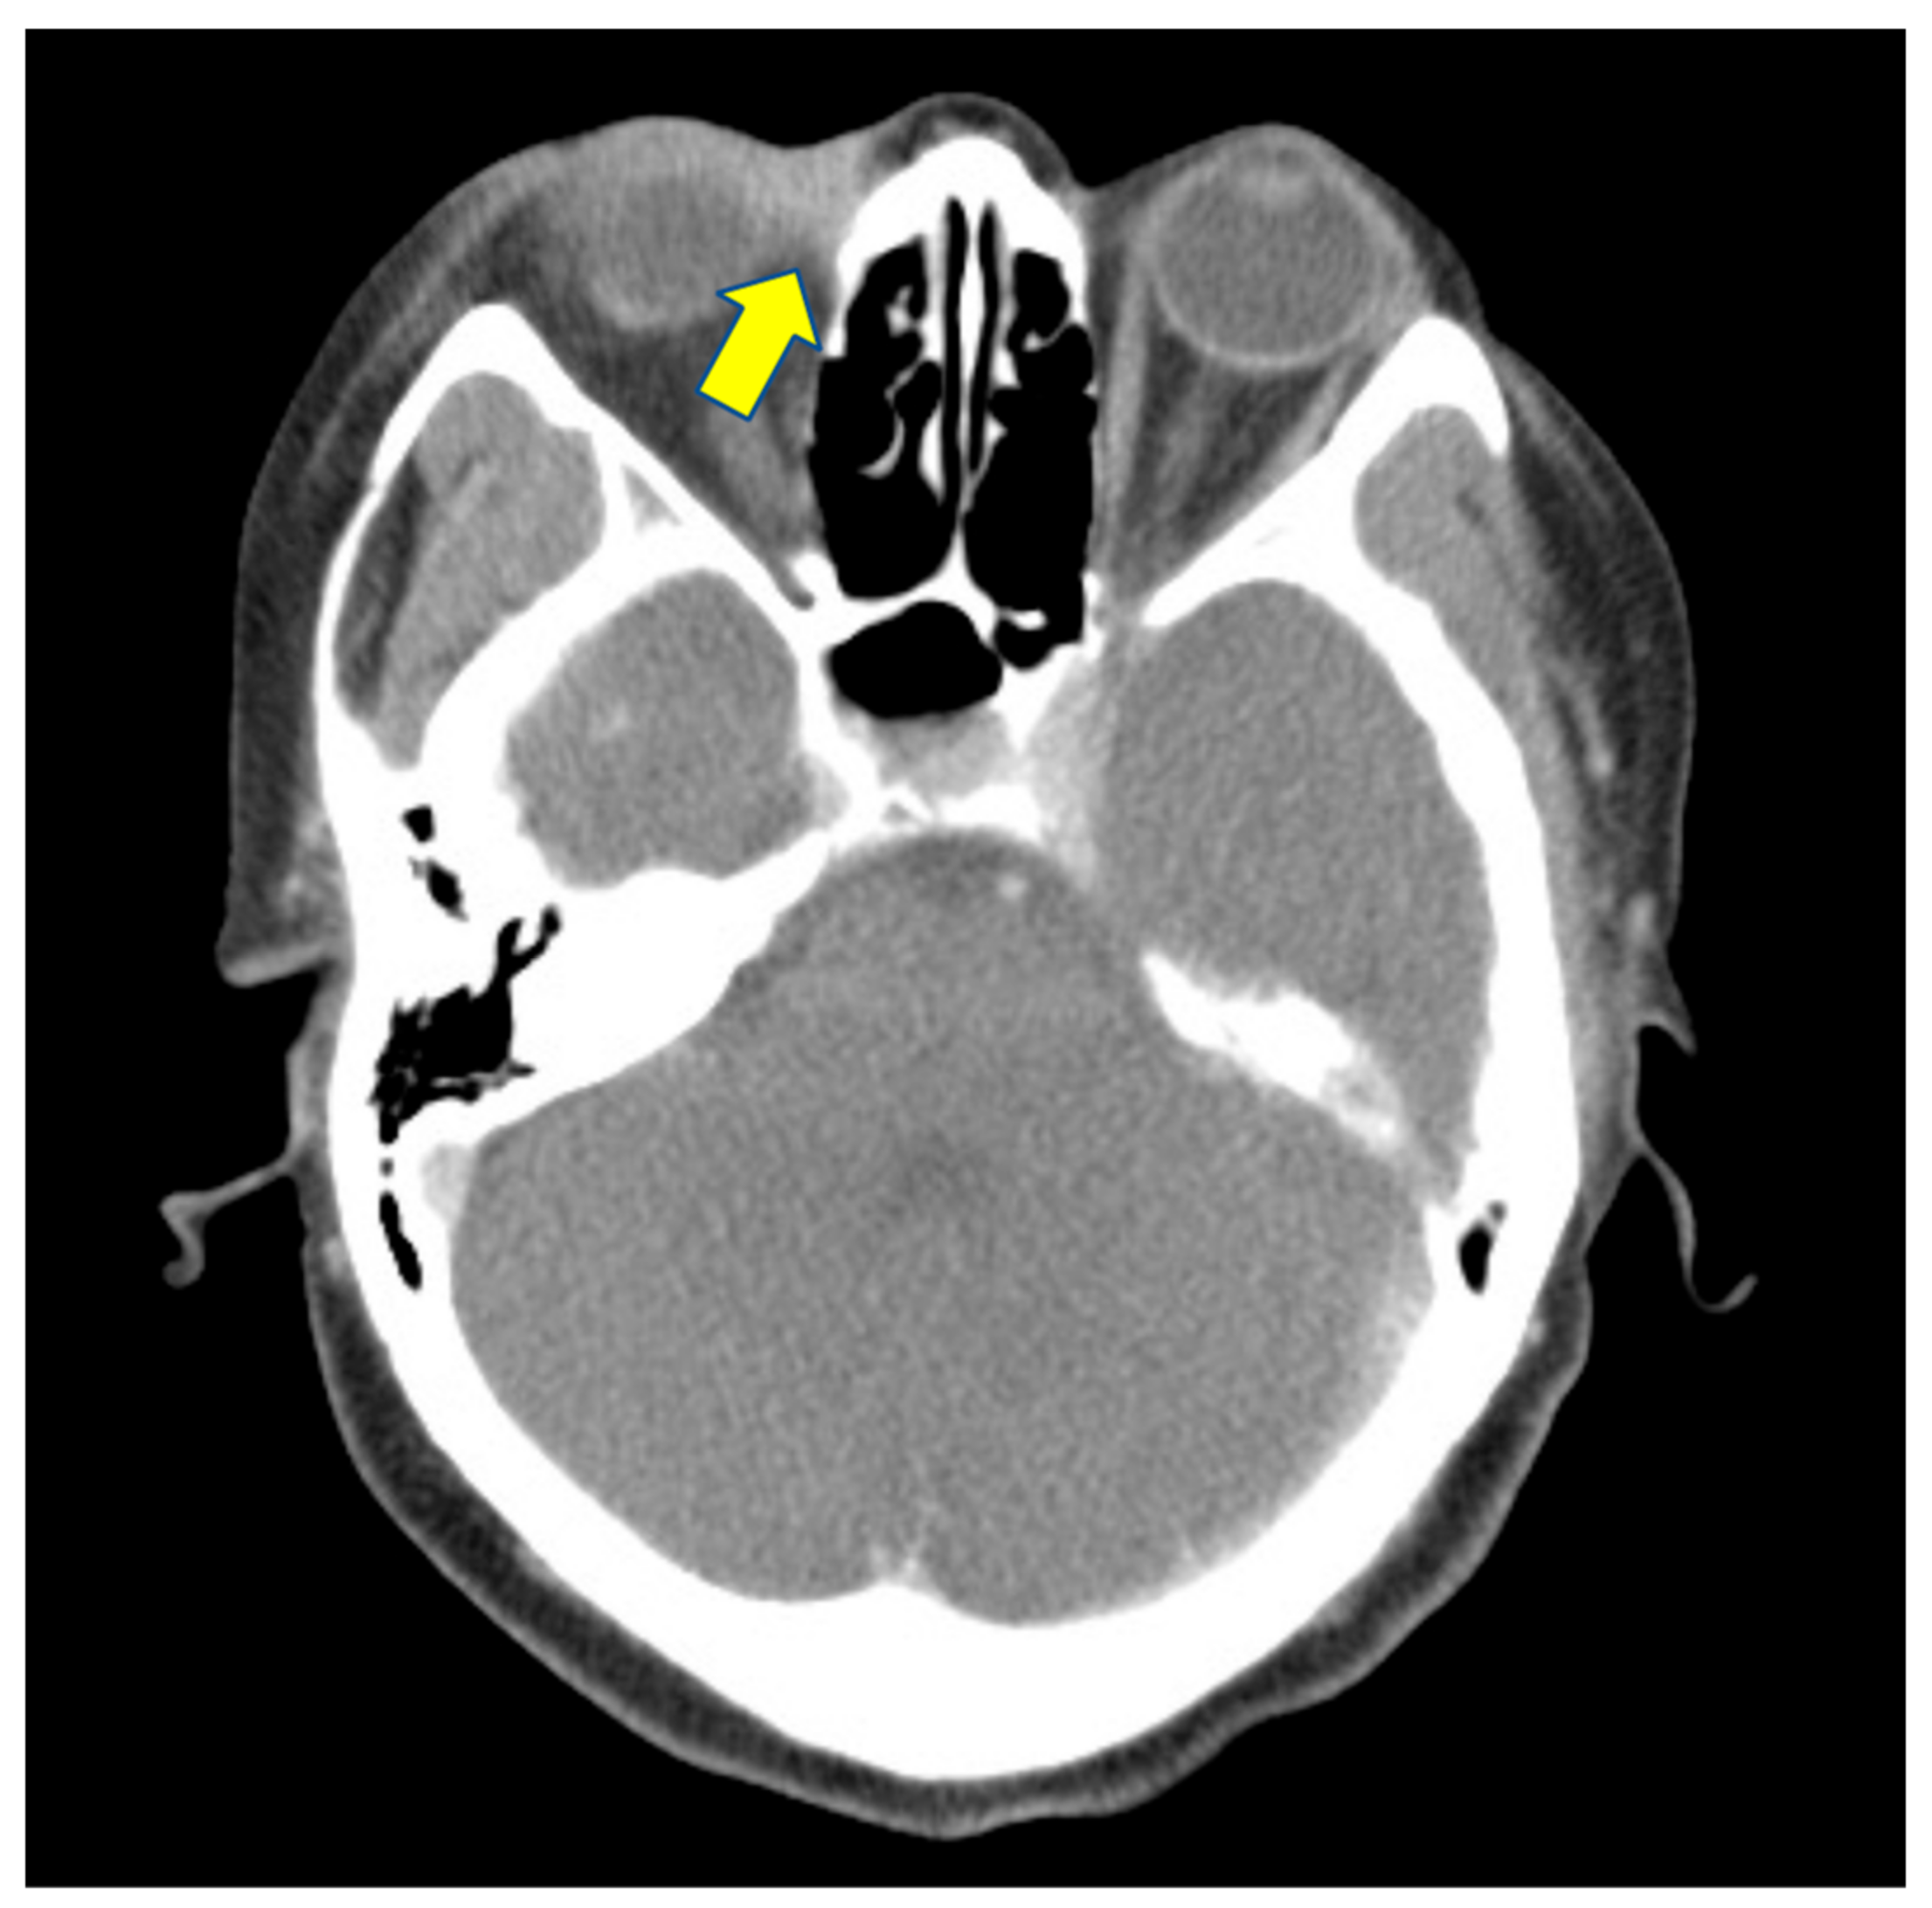

She came to our ophthalmic clinic due to a poor-healing wound overlying the lacrimal sac (Figure 1), accompanied by epiphora and periorbital redness. We irrigated the right nasolacrimal duct and found an obstruction with clear backflow. Other ocular examinations were unremarkable. Laboratory data revealed leukocytosis (13,860/uL) without left shift. Head and neck computed tomography showed enhanced lesion over the right medial periocular area with involvement of the lacrimal sac (Figure 2). Periorbital cellulitis was initially suspected and treated with antibiotics vancomycin and ceftriaxone. However, there was no clinical improvement, whereas wound culture had no growth of bacteria. Biopsy was performed at the ulcerated site, and the pathological studies revealed granulomatous inflammation with a considerable amount of foamy histiocytes and a positive CD-68 stain representing macrophage. Many mycobacteria bacilli inside the histiocytes were observed via acid-fast staining (Figure 3). Later, tuberculosis culture results showed Mycobacterium avium complex (MAC), a slow-growing nontuberculous mycobacterium (NTM). She was then treated with azithromycin, ethambutol, and rifabutin for a year. The ulcerated wound was healed, but the symptom of epiphora persisted.

Figure 2.

Head and neck computed tomography showed enhanced lesion over the right medial periocular area with involvement of lacrimal sac (arrow).